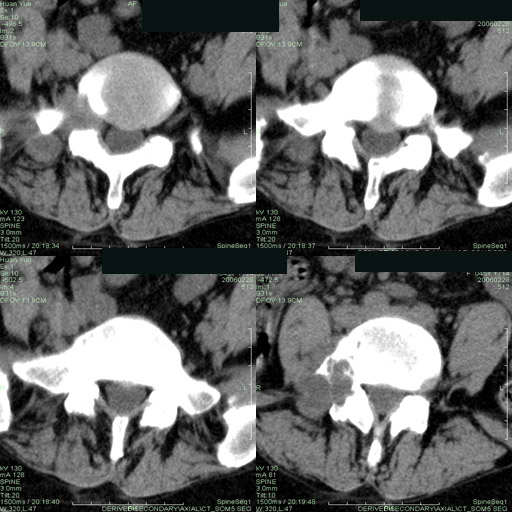

以下是引用听蝉观竹在2006-3-5 23:09:00的发言:[br]这个病例不考虑神经源性肿瘤,首先考虑转移瘤,因为它不是受压造成骨质吸收,而是从骨骼的松质部分由中心向外破坏的,不仅仅是横突,而且同侧椎弓根也破坏了。[br]神经源性肿瘤-----受压造成骨质吸收。[br]转移性肿瘤------从骨骼的松质部分由中心向外溶骨破坏,多见椎弓根也破坏。

以下是引用徐大夫在2006-3-5 20:32:00的发言:[br]骨缺损区边缘有硬化,结合部位,考虑神经源性良性肿瘤。